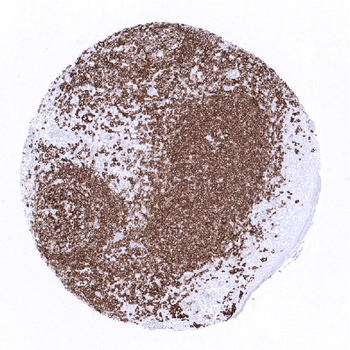

CD20 antibody validated for immunohistochemistry on 76 different Normal Tissues

In the tonsil, many lymphocytes stain positive while the surface epithelium is CD20 negative.

The thymus contains a relatively low fraction of CD20 positive B-lymphocytes.

Strong CD20 staining of a germinal centre in the appendix mucosa while epithelial cells are completely negative.